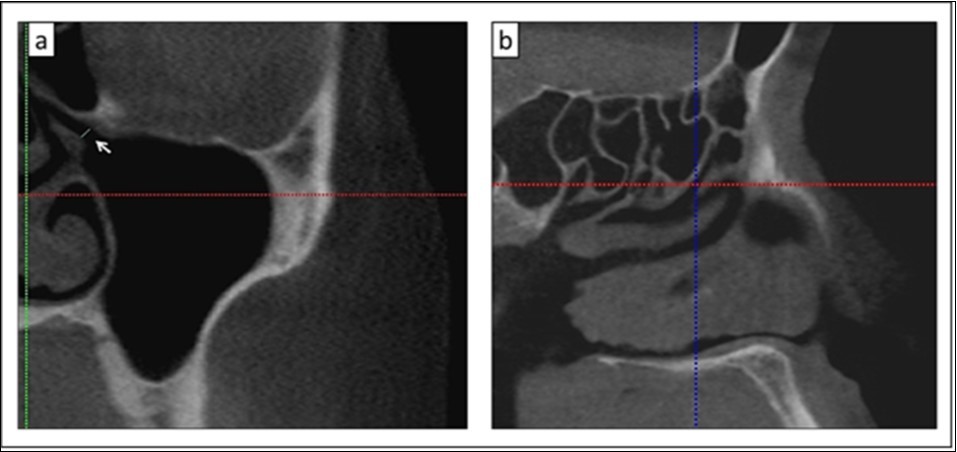

To ensure the accuracy of the anatomical structures depictions, all CBCT examinations were reviewed by a trained oral and maxillofacial radiologist before and after the measurements. The location of the primary maxillary ostium along the course of the hiatus semilunaris was identified. Subsequently, the maxillary sinus ostium diameter (mm) was measured from the inferior uncinate process to the superior lower bony portion of the ethmoidal sinus in the coronal view (Figure 2a). The diameter was measured three times and subsequently the averaged reading was calculated to ensure reproducibility and reduce any subjective bias. The data was recorded and classified according to the ethnic groups and their gender.

Thereafter, the location of maxillary sinus ostium was determined, it was marked with the horizontal and vertical axis lines in the coronal section (Figure 2a). When the sagittal section window was reviewed, the position of the point/marking was determined along the hiatus semilunaris (Figure 2b). The position of the primary maxillary sinus ostium at the hiatus semilunaris were recorded and classified as being in the anterior third, middle third or posterior third of this hiatus. The hiatus semilunaris is interpreted as the opening between the anterior surface of the bulla ethmoidalis and the free edge of the uncinate process 9.

Figure 2.a) Measurement of the primary maxillary ostium between the lower bony part of ethmoid and the uncinate process (white arrow); b) Location of the primary maxillary ostium in the coronal section (a) which is observed in the sagittal section (crosshair lines)

a) Measurement of the primary maxillary ostium between the lower bony part of ethmoid and the uncinate process (white arrow); b) Location of the primary maxillary ostium in the coronal section (a) which is observed in the sagittal section (crosshair lines)